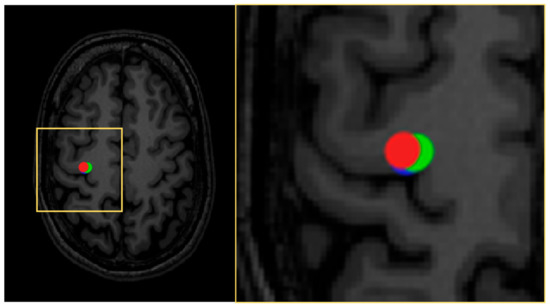

- Julkunen, P. Methods for estimating cortical motor representation size and location in navigated transcranial magnetic stimulation. J. Neurosci. Methods 2014, 232, 125–133. [Google Scholar] [CrossRef]

- Reijonen, J.; Pitkanen, M.; Kallioniemi, E.; Mohammadi, A.; Ilmoniemi, R.J.; Julkunen, P. Spatial extent of cortical motor hotspot in navigated transcranial magnetic stimulation. J. Neurosci. Methods 2020, 346, 108893. [Google Scholar] [CrossRef]

- Sollmann, N.; Hauck, T.; Obermuller, T.; Hapfelmeier, A.; Meyer, B.; Ringel, F.; Krieg, S.M. Inter- and intraobserver variability in motor mapping of the hotspot for the abductor policis brevis muscle. BMC Neurosci. 2013, 14, 1–7. [Google Scholar] [CrossRef]